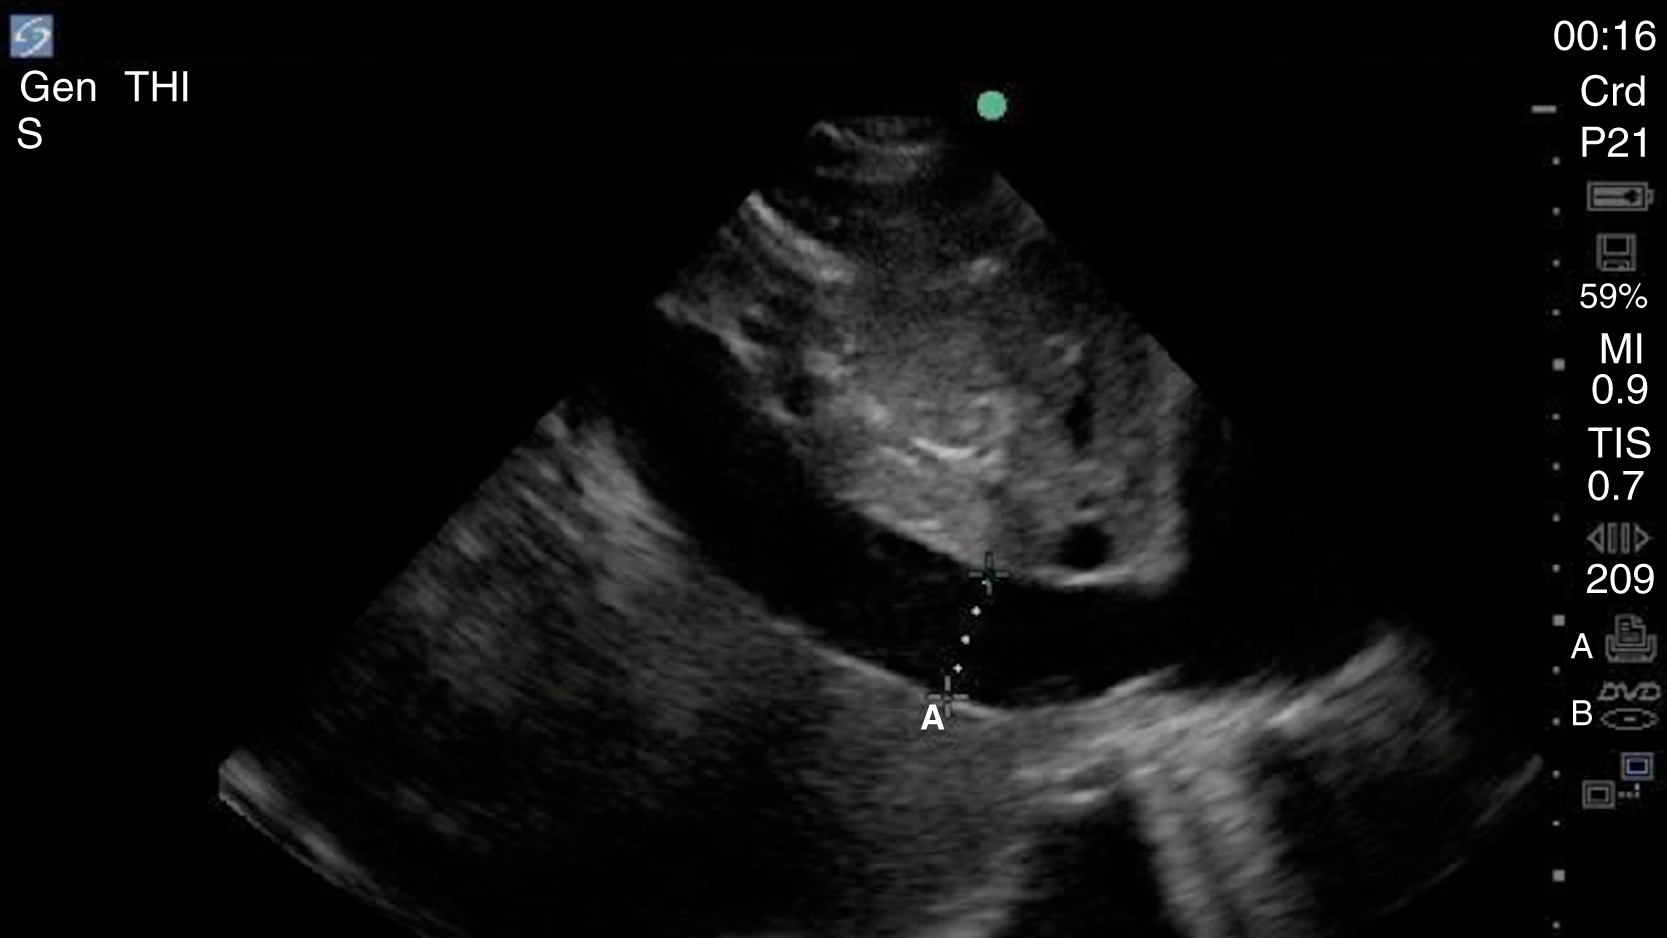

Pericardial fluid is typically anechoic, although it can contain internal echoes in cases of pericardial hemorrhage or infection. Large pericardial effusions are usually circumferential but can be loculated. As a result, assessment for pericardial effusion should include multiple views, when feasible, to confirm diagnosis and to avoid mistaking the epicardial fat pad for a pericardial effusion. Although cardiac tamponade is a clinical diagnosis, there are several suggestive echocardiographic features, including diastolic collapse of the RV ( Video e3.9 ), loss of respiratory variation of the IVC ( Fig. e3.11 ), and transvalvular flow velocity paradoxus.

Plethoric IVC showing where to take a measurement.

Assessment for global LV systolic function can be performed with visual estimation ( Video e3.10 ) and/or assessment of E-point septal separation (EPSS). EPSS is the distance between the anterior mitral valve leaflet and the ventricular septum measured using M-mode. A distance greater than 7 mm is abnormal, with larger measurements correlating to worsening systolic function. Emergency clinicians should recognize that accurate visual estimation of global LV systolic function requires experience and may prefer to categorize systolic function dichotomously as depressed or normal.